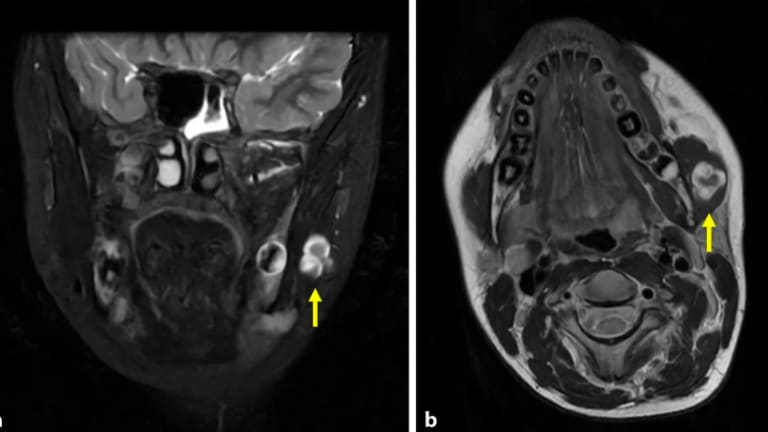

Unklare Raumforderung im M. masseter

Abb. 1: Natives Kopf-Hals-Magnetresonanztomogramm der Patientin in a koronarer Schichtung (STIR T2 frFSE) und b axialer Schichtung (T2 FSE). Deutlich erkennbar ist die hyperintense Raumforderung (Pfeil). STIR „short tau inversion recovery“, frFSE „fast relaxation fast spin echo“, FSE „fast spin echo“.

Schmerzhafte Schwellung der Wange bei einem Kind (Natives Kopf-Hals-Magnetresonanztomogramm der Patientin)